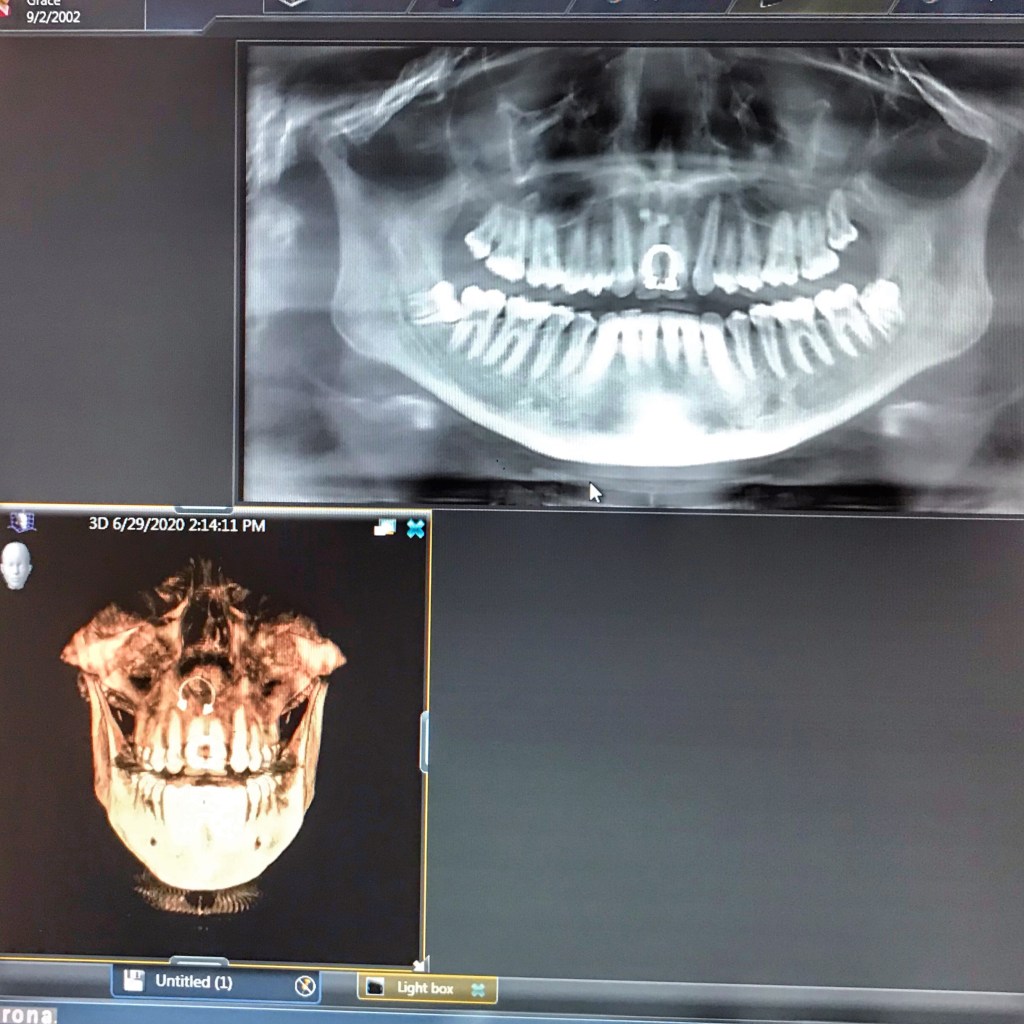

That’s because she had all four wisdom teeth out on Tuesday and yesterday was a very bad day for her. She’s my third kid to have all four wisdom teeth yanked out and by far, she has had the worst post-surgery effects. Immediately after surgery, she felt nauseated and the nausea prevented her from taking effective pain medication and then we realized that dairy is definitely a problem for her on top of everything else.